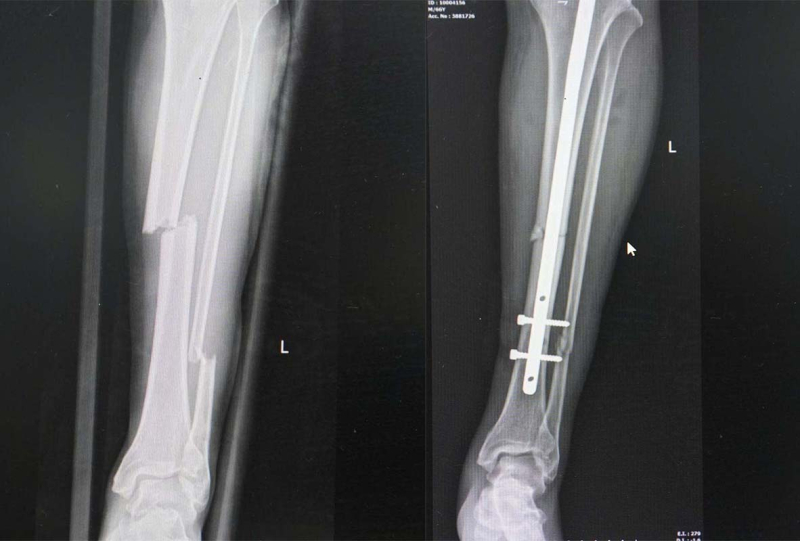

Mới đây, các bác sĩ Khoa Chấn thương chỉnh hình đã thực hiện phẫu thuật kết hợp xương không mở ổ gãy điều trị cho bệnh nhân Trần V L (66 tuổi, ở phường Việt Hưng, tỉnh Quảng Ninh). Người bệnh sau tai nạn giao thông bị đau nhiều vùng cẳng chân trái và hạn chế vận động. Kết quả chụp xquang có hình ảnh gãy kín 1/3 giữa hai xương cẳng chân trái.

Phim chụp tổn thương gãy xương của bệnh nhân trước và sau phẫu thuật

Dưới sự hỗ trợ của hệ thống xquang di động C-arm, Ekip phẫu thuật của bác sĩ CKII Vũ Quang Nghĩa – Trưởng Khoa Chấn thương – chỉnh hình, Bệnh viện Bãi Cháy đã tiến hành phẫu thuật kết hợp xương bằng kỹ thuật nắn kín ổ gãy dưới màn hình tăng sáng C-arm và đóng đinh nội tủy kín có chốt cố định xương. Ca phẫu thuật diễn ra thành công, trục xương đảm bảo vững chắc, vết mổ thẩm mỹ.